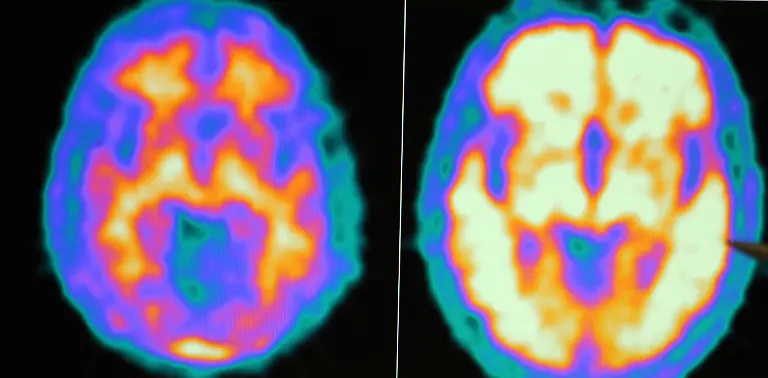

In sich selbst gefangenAutismus

Bis heute können die Ursachen für Autismus nicht klar benannt werden. Die unheilbare Entwicklungsstörung kann in verschiedenen Schweregraden auftreten. Die Ausprägung ist so vielfältig wie die Menschen selbst. Rund 70 Millionen Menschen sind weltweit betroffen.